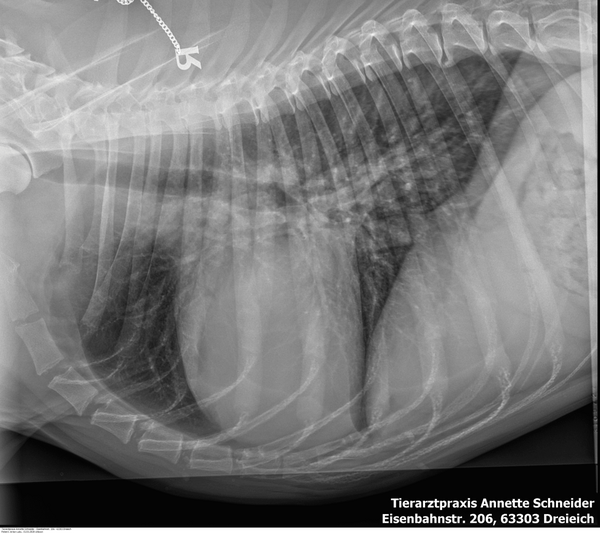

Sammy, ein fast 13 jähriger Mischlings-Rüde, wurde uns wegen seines stark aufgetriebenen Bauchs vorgestellt.

Eine Röntgenuntersuchung zeigte eine Masse, die den gesamten Bauchraum ausfüllte und alle anderen Organe stark verdrängte. Sie führte bereits zu einer erschwerten Atmung.

Trotz Sammys fortgeschrittenem Alter entschied sich sein Herrchen mutig zu einer Operation.

In der Operation zeigte sich, dass es sich um eine riesige, flüssigkeitsgefüllte Masse des Gekröses handelte. Wir entfernten sie erfolgreich. Vor der Operation wog Sammy 20 kg, danach nur noch 16,2 kg. Die Masse wog also 3,8 kg. Fast ein Viertel seines ursprünglichen Gewichts.

Die histopathologische Untersuchung ergab eine gutartige Veränderung.